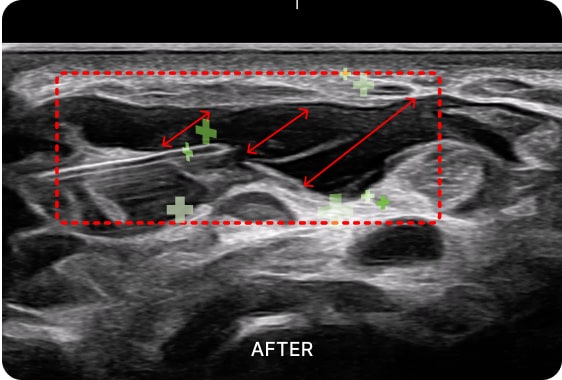

초음파 검사를 통해

수부건초염 통증의 직접적인

원인을 확인할 수 있습니다.

손목에 존재하는 1~6 구획의 건초 상태를

진단하고 정확한 부위를 치료하여 손목과

손가락 통증을 해결합니다.

01. PDRN 약침

PDRN 약침은 인체의 DNA와 90% 이상 유사한 구조로 세포 증식을 활성화하여

손상된 조직을 복구하는 효과가 뛰어납니다. 초음파를 활용하여 신경을 압박하는

염증을 박리하고 손상된 조직을 재생합니다.